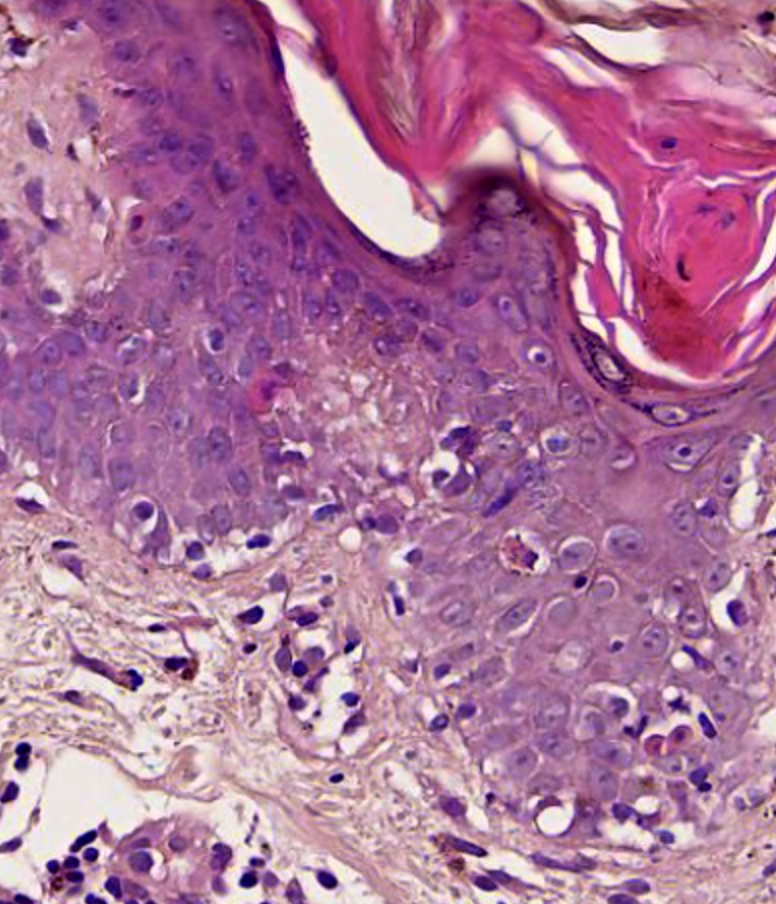

Microscopic (histologic) description

- Interface dermatitis with variable degrees of basal layer vacuolization and scattered cytoid bodies (Lupus 2012;21:577)

- Dyskeratotic keratinocytes extending into upper spinous layers is a very characteristic but rare finding of SCLE (J Cutan Pathol 2001;28:1)

- Hyperkeratosis / parakeratosis may be present

- Sometimes focal hypergranulosis

- Superficial and sometimes superficial and deep perivascular lymphocytic infiltrate (Dermatol Ther (Heidelb) 2021;11:131)

- Periadnexal mononuclear cell infiltrate may be present (Dermatol Ther 2021;11:131)

- Dermal mucin, which may be highlighted with Alcian blue or colloidal iron

- Epidermal atrophy, follicular plugging, basement membrane thickening, dermal mucin and pigment incontinence may be present but less prominent than in chronic lupus erythematosus

Microscopic (histologic) images

- Comment: Epidermal thinning with hyperkeratosis. Vacuolar interface dermatitis with dyskeratotic keratinocytes that extend into upper spinous layers. Superficial perivascular lymphocytic infiltrate. Correlate with clinical and laboratory testing. These findings are more consistent with SCLE subtype.

A 50 year old man with a history of recent onset hypertension treated with enalapril presented with a 1 month history of annular and erythematous polycyclic plaques with peripheral scale that were located in sun exposed areas. No other systemic manifestations were found. Serologic test results were positive for ANA, anti-Ro / SSA and anti-La / SSB, while negative for ds-DNA, anti-histone and anti-Smith. Which histopathological finding that can be seen in this image is more characteristic of the patient's clinical type?

- Dyskeratotic keratinocytes extending to upper layers

A. Dyskeratotic keratinocytes extending to upper layers